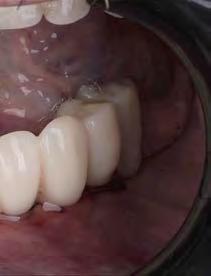

E-max CAD sobre implante

E-max CAD sobre diente natural

El innovador Disilicato de Litio (LS2) del sistema de cerámica vítrea IPS e.max CAD no solo ofece una altísima estética sino que también es de 2,5 a 3 veces más resistente 360 MPa que el resto de cerámicas de vidrio. Por ello, este material cubre todos los requerimientos estéticos y también representa una alternativa eficiente a las restauraciones unitarias de Zr02 (Zirconio).

El innovador Disilicato de Litio (LS2) del sistema de cerámica vítrea IPS e.max CAD no solo ofrece una altísima estética sino que también es de 2,5 a 3 veces más resistente 360 MPa que el resto de cerámicas de vidrio. Por ello, este material cubre todos los requerimientos estéticos y también representa una alternativa eficiente a las restauraciones unitarias de ZrO2. (Zirconio)

IPS e.max está avalado por la experiencia clínica que ha demostrado durante años, tanto en estética como en resistencia. La amplitud de elección del material, según el caso, en conjunción con la técnica empleada en nuestro laboratorio dotarán a los trabajos de la mayor estética para sus pacientes.